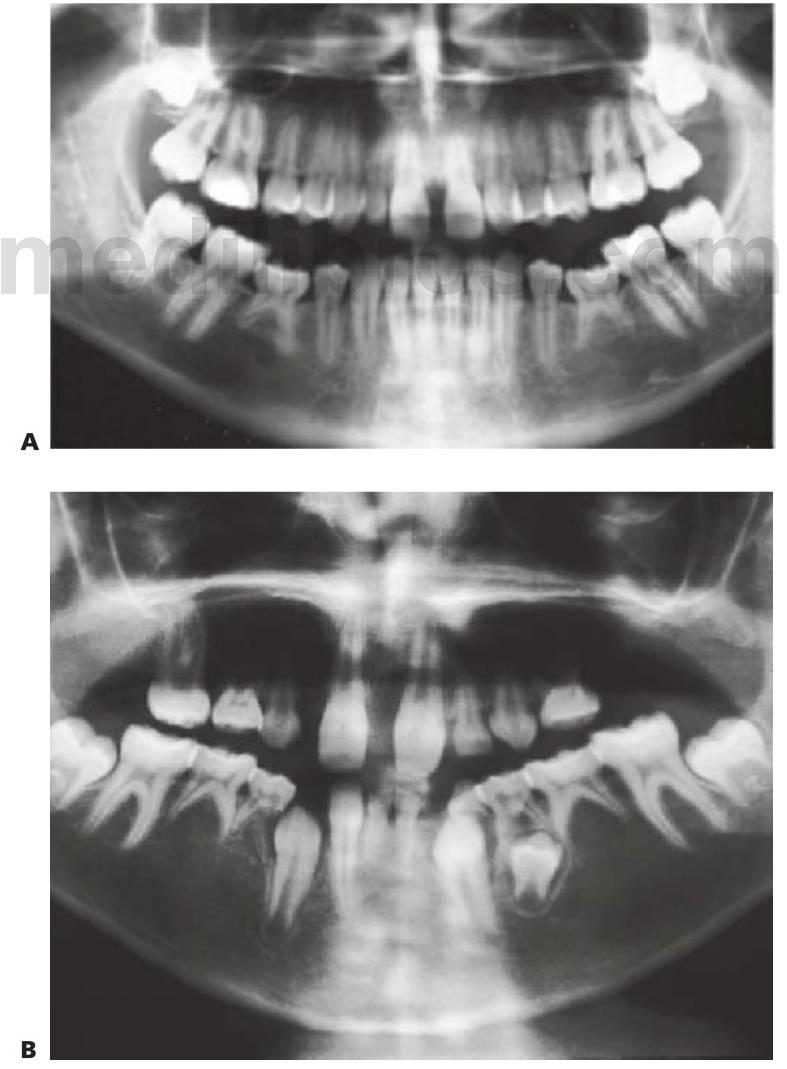

Hipodoncia, oligodoncia y anodoncia son los términos que designan los diferentes grados de progresión de la ausencia de dientes, si bien el término hipodoncia es el más utilizado debido a que se refiere a un número indeterminado de dientes ausentes (fig. 9.1 A). La oligodoncia designa la ausencia de seis dientes o más, y la anodoncia la ausencia completa de dientes. Todos estos casos se producen debido a un fallo en el desarrollo. El término «dientes ausentes congénitamente» no puede aplicarse a la dentición permanente, ya que estos dientes comienzan su desarrollo después del nacimiento, y tampoco a la dentición temporal ya que esa ausencia dental no puede determinarse de forma clínica en el momento de nacer; asimismo, el término «anodoncia parcial» carece de sentido. Sucede con frecuencia que los grados de hipodoncia aparezcan de manera esporádica o bien tengan un componente hereditario. Cuando a un individuo le faltan muchos dientes se debe estudiar a otros miembros de la familia afectados.

- Varios dientes ausentes (fig. 9.1 B).

Los dientes son pequeños y cónicos y a menudo presentan un gran diastema anterior (fig. 9.3). Sus manifestaciones pueden limitarse a un solo diente ausente o a un incisivo lateral en clavija (v. hipótesis de Lyon, más adelante) y las mujeres heterocigóticas suelen ser diagnosticadas gracias a este tipo de dentición.

Dentro del grupo de displasias ectodérmicas, se observan asimismo modos de herencia autosómica tanto dominante como recesiva. Si se compara con la displasia ectodérmica hipohidrótica ligada al cromosoma X, en las familias con este trastorno no existen diferencias tan acentuadas en cuanto al grado de trastorno entre los hombres y las mujeres (figs. 9.2A, 9.4). Se han identificado mutaciones en el gen MSX1 (4p16.1) en familias con terceros molares y segundos premolares ausentes con o sin paladar hendido/labio leporino, así como en familias con el síndrome diente-uña (Witkop). Se han observado mutaciones del gen PAX9 (14q12-q13) en otras familias con dientes ausentes de forma autosómica dominante.